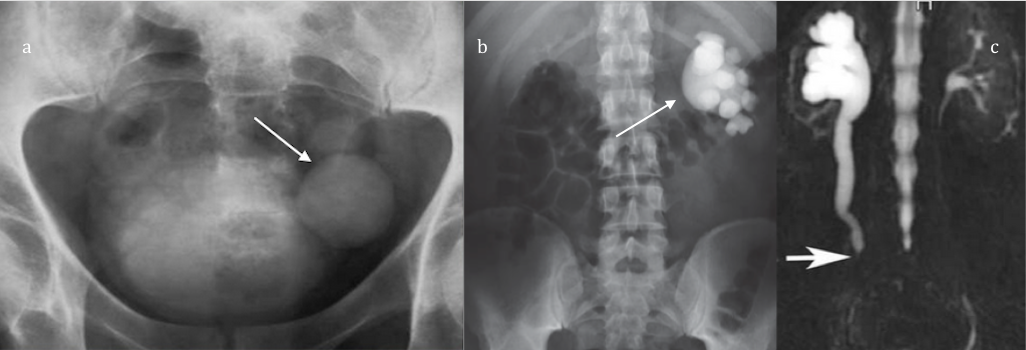

Obstrucción de la vía urinaria: Existen múltiples causas de obstrucción de la vía urinaria, como por ejemplo, la hiperplasia benigna de la próstata, litiasis urinaria, un tumor que obstruya el lumen urinario… etc. Todas estas condiciones son capaces de producir estasis urinaria

– Litiasis: La presencia de litiasis muchas veces favorece la persistencia de gérmenes en la vía urinaria, pues los antibióticos no son capaces de erradicarlas completamente de las mismas.